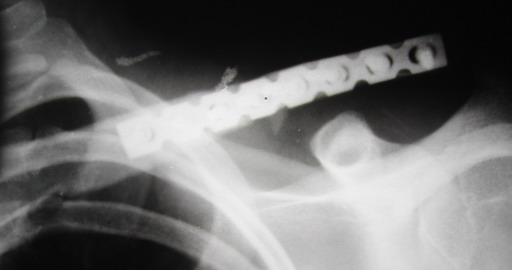

БИОС, пластина, штифт с проволочными петлями, аппарат консольный или комбинация - это решается на уровне местном. Однако в свое время аппарат

Во время стажировки в Австрии не мог не поинтересоавться, как австрийские хирурги лечат переломы ключицы. Оказалось, при переломах без смещения или с небольшим смещением накладывают восьмиобразную повязку, в остальных случаях выполняют остеосинтез пластинами.